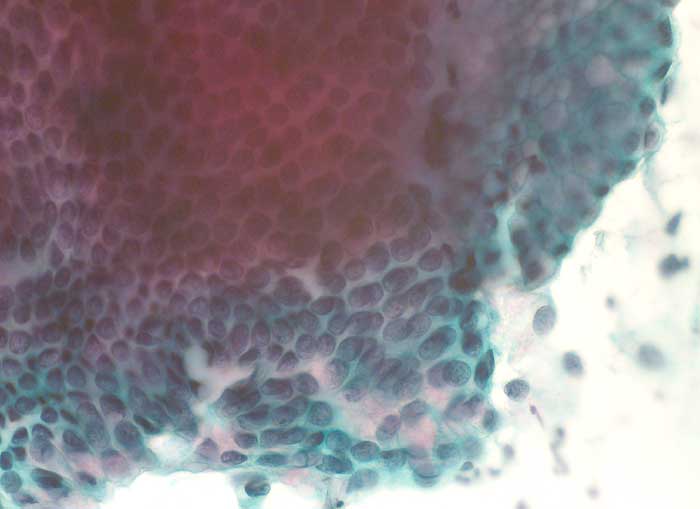

Die Ausstriche des ACIS sind zellreich und enthalten atypische Zylinderzellen mit grossen Kernen. Diese bilden flache Verbände, die in der Aufsicht ein Honigwabenmuster, bei seitlicher Betrachtung ein Palisadenmuster und eine Pseudostratifikation der Kerne erkennen lassen. Die Kerne sind im Vergleich zum normalen Zylinderepithel deutlich grösser und enthalten einen vergrösserten Nukleolus. Eine Hyperchromasie ist nicht immer vorhanden und das granuläre Chromatin ist regelmässig verteilt. Der zytologische Nachweis von atypischen Zylinderepithelien sollte histologisch weiter abgeklärt werden.